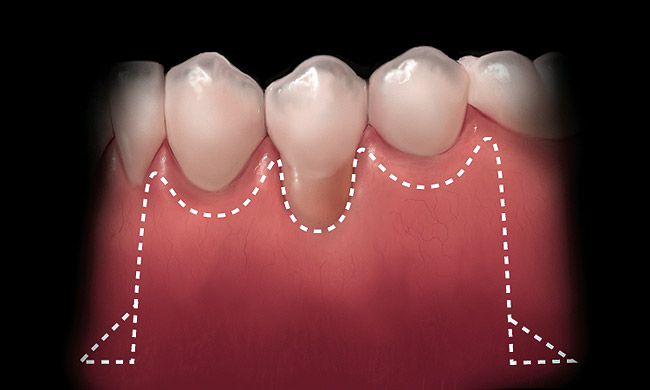

A local anesthetic should be administered mesially and distally of the intended surgical site. A sulcular incision is then started one tooth distal to the tooth/teeth to be treated. The incision is continued to the opposing side one tooth from the site requiring treatment. The papilla should be spared and left attached to the lingual soft tissue to help eliminate soft tissue loss interproximally. Vertical releasing incisions are next made bilaterally and carried beyond the mucogingival junction, ending in Burrow’s triangles (Figure 1). A Burrow’s triangle is used to relieve tension at the most apical extent of a vertical releasing incision to improve flap mobility and achieve tension-free closure.9

Figure 1  Incisions illustrated with Burrow’s triangles located apical to the mucogingival junction.

Figure 1